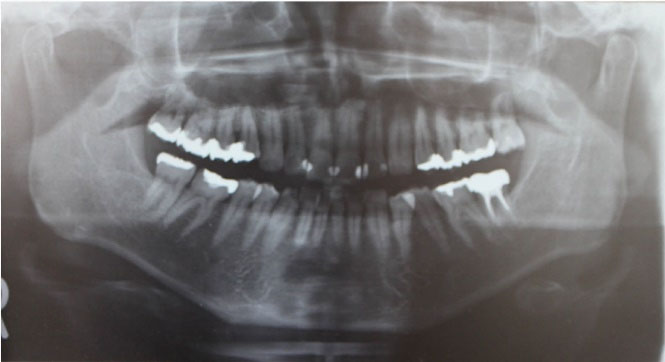

A 47-year-old man visited our hospital with a chief complaint of discomfort and slight intermittent pain in the maxillary gingiva. He had noticed a diffuse swelling in the anterior maxillary area over the past 6 months. On oral examination, a 30 × 25-mm solitary well-defined swelling was seen in the maxillary labial vestibule, extending from the right central incisor to the first molar. The swelling was tender and fluctuant on palpation (). The right maxillary teeth were not mobile and exhibited a vital pulp reaction. The panoramic radiograph revealed a large radiolucent area close to the roots of teeth #12 to #16, extending to the right orbital rim, including two radiopaque structures resembling teeth (). A computed tomographic (CT) examination revealed an oval unilocular radiolucent lesion, approximately 50 × 45 × 35 mm in size with a well-defined border in the right maxilla and including two supernumerary teeth ().

Figure 2. The panoramic radiograph showing a large radiolucent area (white arrowhead), including two radiopaque tooth-like structures (white arrow)

Dentigerous cysts may appear radiographically as well-defined unilocular or multilocular radiolucent lesions, including the crown of an unerupted tooth. 7 Images of supernumerary teeth are clearly seen radiographically. Panoramic radiographs, plain radiographs of the maxillary sinus using Waters’ method, and CT, in particular, are useful for determining the location of the tooth. CT imaging is the gold standard modality for confirming the location of the unerupted tooth and the spread of the cyst. 1,2 In the present case, panoramic radiography and CT were performed to diagnose the intra-sinus situation. The relationship between the original sinus and the cystic cavity was not obvious on the panoramic radiograph because the vertebra overlapped the sinus structure. Since a thin septum was evident between the original sinus and the cystic cavity on CT, we could confirm that the lesion existed within the maxillary bone, separate from the sinus.